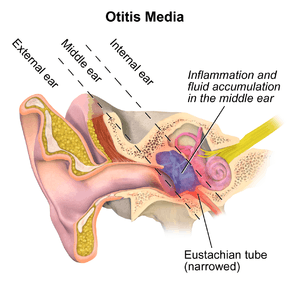

Otitis media is a group of inflammatory diseases of the middle ear.[1] The two main types are acute otitis media (AOM) and otitis media with effusion (OME).[2] AOM is an infection of abrupt onset that usually presents with ear pain. In young children this may result in pulling at the ear, increased crying, and poor sleep. Decreased eating and a fever may also be present. OME is typically not associated with symptoms.[3] Occasionally a feeling of fullness is described. It is defined as the presence of non-infectious fluid in the middle ear for more than three months. Chronic suppurative otitis media (CSOM) is middle ear inflammation of greater than two weeks that results in episodes of discharge from the ear. It may be a complication of acute otitis media. Pain is rarely present.[4] All three may be associated with hearing loss.[1][2] The hearing loss in OME, due to its chronic nature, may affect a child's ability to learn.[4]

The common cause of all forms of otitis media is dysfunction of the Eustachian tube.[13] This is usually due to inflammation of the mucous membranes in the nasopharynx, which can be caused by a viral URI, strep throat, or possibly by allergies.[14] Because of the dysfunction of the Eustachian tube, the gas volume in the middle ear is trapped and parts of it are slowly absorbed by the surrounding tissues, leading to negative pressure in the middle ear. Eventually the negative middle-ear pressure can reach a point where fluid from the surrounding tissues is sucked in to the middle ear's cavity (tympanic cavity), causing a middle-ear effusion. This is seen as a progression from a Type A tympanogram to a Type C to a Type B tympanogram.

By reflux or aspiration of unwanted secretions from the nasopharynx into the normally sterile middle-ear space, the fluid may then become infected — usually with bacteria. The virus that caused the initial URI can itself be identified as the pathogen causing the infection.[14]